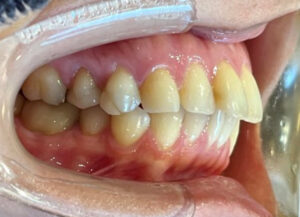

メンテナンスでいつもお越しいただいている長年の患者様が、

「前歯をもう少し綺麗になおしたい」「歯茎との境が黒くなっているのが気になる」とのことで、

仕事や生活の都合上、タイミングがあったので今回審美治療をスタートすることにしました!

元々、上の前歯に入っている補綴物の状態がこちらです。

歯と歯茎の境が黒くなっているのがわかります。

まずは元々入っている補綴物を外し、仮の歯を入れていきます。

仮歯を入れた状態がこちらです。

歯科治療において、仮歯の役割はとても重要になります。

嚙み合わせの状態や、審美的な見た目など、

仮歯の段階で何かしらのエラーに気づくことができれば事前に修正することができます。

歯肉が安定してきたら、最終の補綴物を入れる前に

天然の歯にホワイトニングをかけていきました。

白くなった歯に合わせて最終の補綴物を入れていきます。

そして前歯にフルジルコニアセラミッククラウンを入れた状態がこちらです。

Before After

歯と歯茎の境もなくしっかりとフィットし、綺麗な仕上がりになりました。

笑顔もとても素敵ですね♪